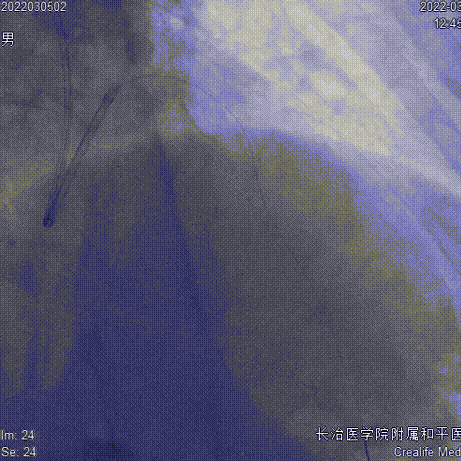

残余狭窄、肌桥

结果